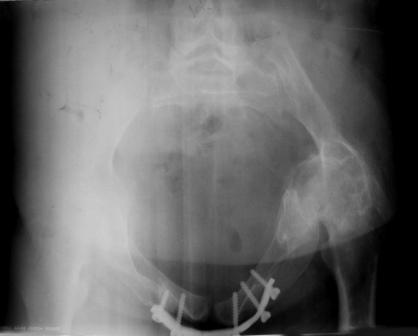

Уважаемые коллеги! Пациентка 32 года с застарелым повреждением таза, после остеосинеза лонного сочленения пластиной. Посоветуйте с выбором тактики и методик лечения.

Получила травму в феврале 2004г в г.Лобытнанги ЯНАО Тюм.обл. Через неделю после поступления выполнен остеосинтез лонного сочленения пластиной. 1,5 месяца на скелетном вытяжении. В последующем ходит при помощи костылей с нагрузкой на правую ногу. Имеется нестабильность половин таза, неправильно-консолидированный перелом левой вертлужной впадины, невропатия седалищного нерва слева. В результате невропатии седалищного нерва сформировалась эквинусная установка левой стопы, парестезии по подошвенной поверхности.

Направлена к нам для устранения патологической установки стопы и эндопротезирования левого тазобедренного сустава, также имеется миграция шурупов пластины, фиксирующей лонное сочленение.

Клинически: ходит на костылях с нагрузкой на правую ногу. Левая стопа в эквинусе. Осевая нагрузка на левую н\конечность болезненна в области левого тазобедренного сустава, при прикосновениях к подошвенной поверхности стопы у пациентки чувство зжения. В левом коленном суставе полный обьем движений, в левом тазобедренном резко ограничено отведение и ротация, укорочение левой н\конечности на 2,5 см. При полипроекционной и функциональной Р-графии выявлена нестабильность левого КПС и лонного сочленения, консолидированный в порочном положении поперечный оскольчатый перелом левой вертлужной впадины с центральным смещением головки бедра. Нами выполнена коррекция деформации левой стопы. Планируется выполнить введение 2 канюлированных илиосакральных винтов слева, реостеосинтез лонного сочленения реконструктивной пластиной, после заживления ран - тотальное эндопротезирование левого тазобедренного сустава.